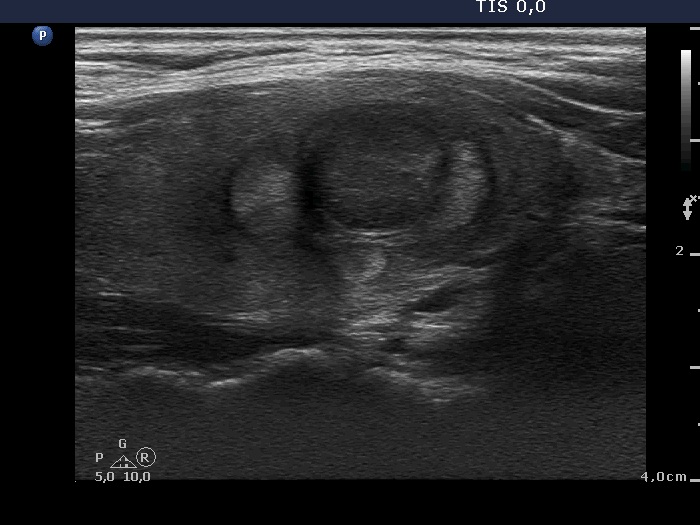

Parathyroid adenoma (histology) - case 671 |

Transverse scan |

Longitudinal scan |

This is a deeply hypoechoic lesion which proved to be a parathyroid adenoma (yellow arrow). The longitudinal images prove that the adenoma was located upper to the thyroid (red arrows). Parathyroid adenomas are almost always hypoechoic.